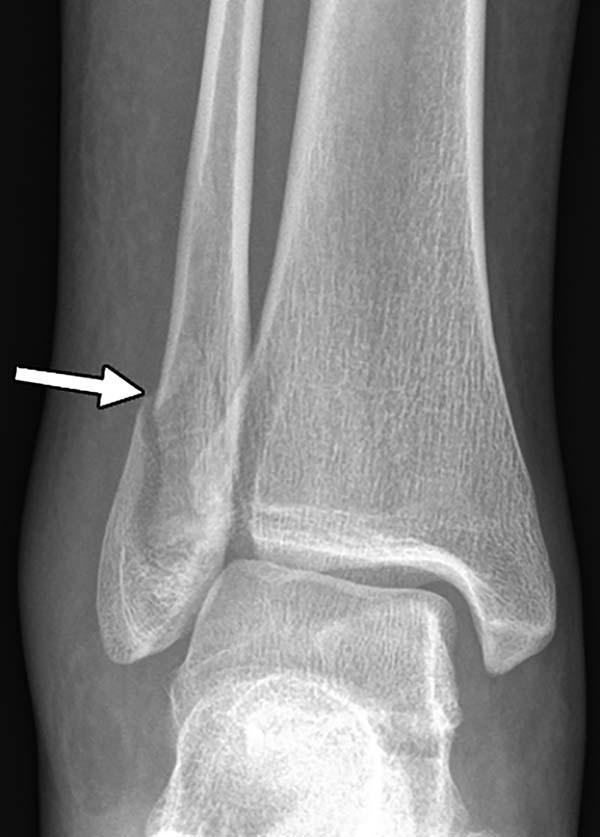

"Radiology has made substantial contributions to the detection of non-accidental trauma in children, and identification of pediatric violence is an essential component of a radiologist's training, but little is known about the role of imaging in the detection of intimate partner violence," said Bharti Khurana, M.D., the study's principal investigator, a radiologist at Brigham and Women's Hospital and assistant professor of radiology at Harvard Medical School in Boston. "Medical images can offer early clues of IPV based on location and pattern of both new and old injuries."

The researchers found that almost all of the intimate partner violence victims were women (96 percent). Victims had a mean age of 34.2 years. Thirty-seven percent were African-American and 28 percent were Hispanic. Victims of intimate partner violence, on average, underwent approximately four times more imaging exams in the preceding five years compared to the control group. Acute fractures and obstetric/gynecologic findings, such as pregnancy loss and intrauterine growth restriction, were associated with two to four times higher odds of domestic violence.